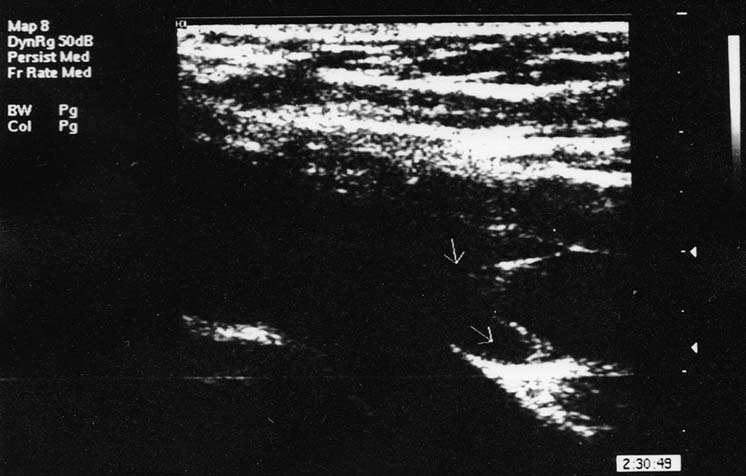

Створки венозных клапанов при дуплексном сканировании выявляются в просвете вены на разных уровнях конечности как тонкие изоэхогенные линейные структуры, которые совершают колебательные движения при дыхании: при вдохе они смыкаются, при выдохе расходятся и прилегают к стенкам вены. Это помогает оттоку крови из клапанных синусов. При выполнении функциональных проб (проксимальной мышечной компрессии, пробы Вальсальвы) створки клапана захлопываются, что при ультразвуковом исследовании можно видеть, как непосредственно, так и за счёт большей эхогенности крови над клапанами из-за её временного стаза (рис. 4).

Рис. 4. Состоятельный клапан бедренной вены при пробе Вальсальвы (В-режим, продольная проекция)

В области синуса клапанов диаметр вены расширяется. Скорость венозного кровотока, регистрируемая в режиме спектральной допплерографии, увеличивается на выдохе или при прекращении мышечной компрессии. В норме при проведении указанных динамических проб может регистрироваться гемодинамически незначимый короткий рефлюксный поток, который обусловлен небольшой задержкой времени закрытия клапана [13]. Время и линейная скорость рефлюксного потока составили в среднем 0,34±0,11 с (не более 0,5 с) и 1,22±0,3 см/c (не более 1,5 см/c), соответственно. Рефлюкс-индекс в норме не превышал 0,4.

При исследовании в вертикальном положении и при спокойном дыхании клапаны магистральных вен приоткрыты, створки находятся под углом 30–40° по отношению к стенке вены. Клапанные створки совершают колебательные движения в просвете вены с амплитудой около 5–15°. В «нишах» клапанных синусов кровь выглядит более эхогенной, что обусловлено, по нашему мнению, её уплотнением и образованием «монетных столбиков» эритроцитов, а также турбулентным кровотоком в этих областях (рис. 5).

Рис. 5. Эхограмма (В-режим, продольная проекция) клапана бедренной вены в состоянии стоя (стрелка внизу указывает на более высокую эхогенность крови в «нише» клапанного синуса)

Такой же феномен можно видеть и в синусах утолщённых и патологически изменённых клапанов не только в вертикальном, но и в горизонтальном положении, что свидетельствует о большей тромбогенности именно зоны клапанных синусов.